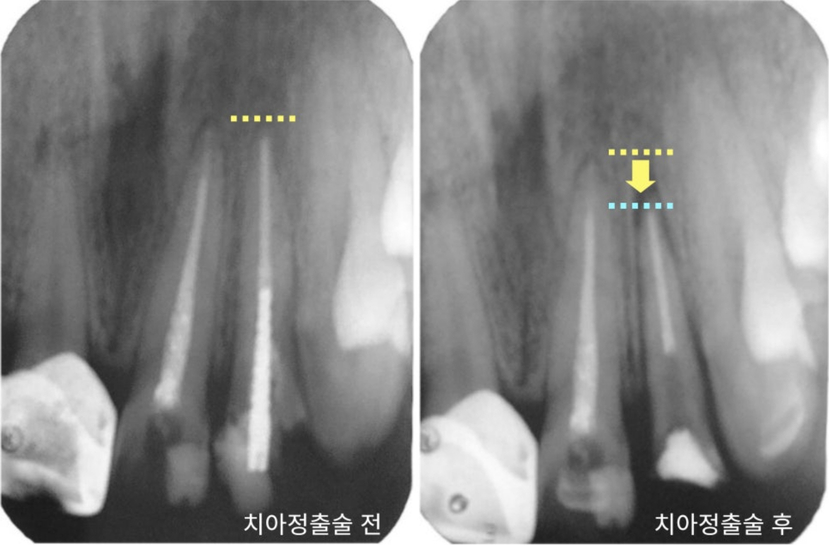

Bất cứ ai thường xuyên đọc blog của tôi đều biết rằng trong

trường hợp một chiếc răng chỉ còn lại chân răng,

có thể cố gắng cứu nó bằng phẫu thuật kéo răng.

▲ Ví dụ về phẫu thuật kéo răng

*Phẫu thuật kéo răng là gì? : Một phương pháp kéo dài tuổi thọ của răng tự nhiên bằng cách nâng răng lên để lộ nhiều đầu răng hơn và cố ý tạo thành vòng sắt.